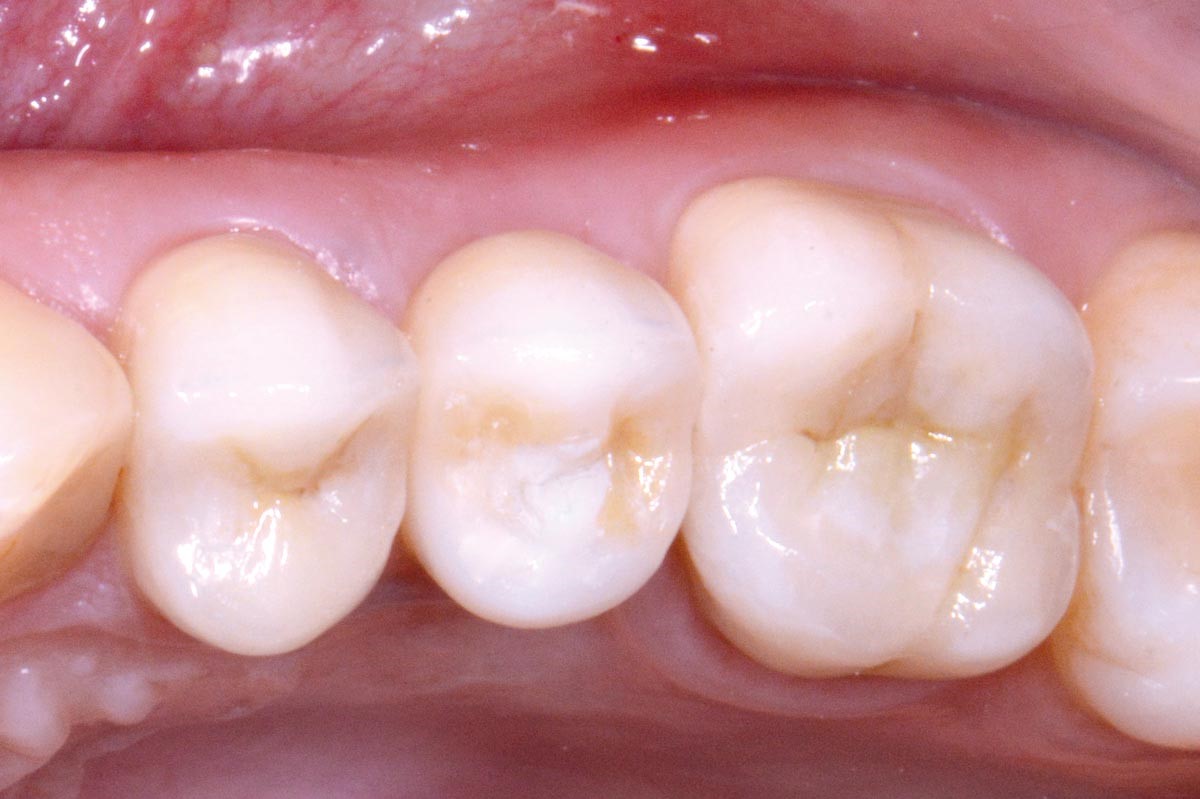

14/16 - Final prosthetic restoration with Zirconia crown at 1 year follow up (Prosthodontist: Dr. Elie Sawdayee)Full bone regeneration in extraction socket augmented with maxgraft® and Jason® membrane – Dr. C. Landsberg

15/16 - Final prosthetic restoration with Zirconia crown at 1 year follow up (Prosthodontist: Dr. Elie Sawdayee)Full bone regeneration in extraction socket augmented with maxgraft® and Jason® membrane – Dr. C. Landsberg